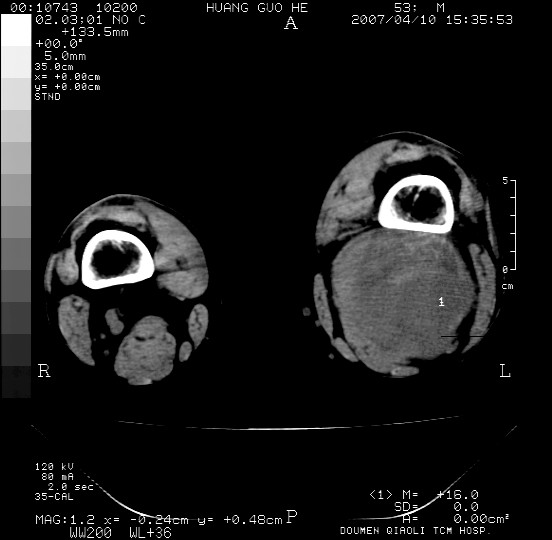

男性,左腘窝包块五个月,逐渐增大,疼痛功能受限,无发热。

查:远端血供差,质地硬。

左侧膝关节后国窝处略低密度软组织肿块,边界清楚,内见脂肪密度及高密度影.多考虑:软组织肿瘤_首选:脂肪纤维瘤.

平滑肌脂肪瘤并出血.应该做个穿刺活检.

左侧腘窝软组织肿块,边缘清晰,其内密度不均,周围骨组织无破坏,病灶增长较快,考虑:恶性病变(腘窝滑膜肉瘤可能),建议穿刺活检。

考虑神经纤维瘤出血,不排除腘窝囊肿出血